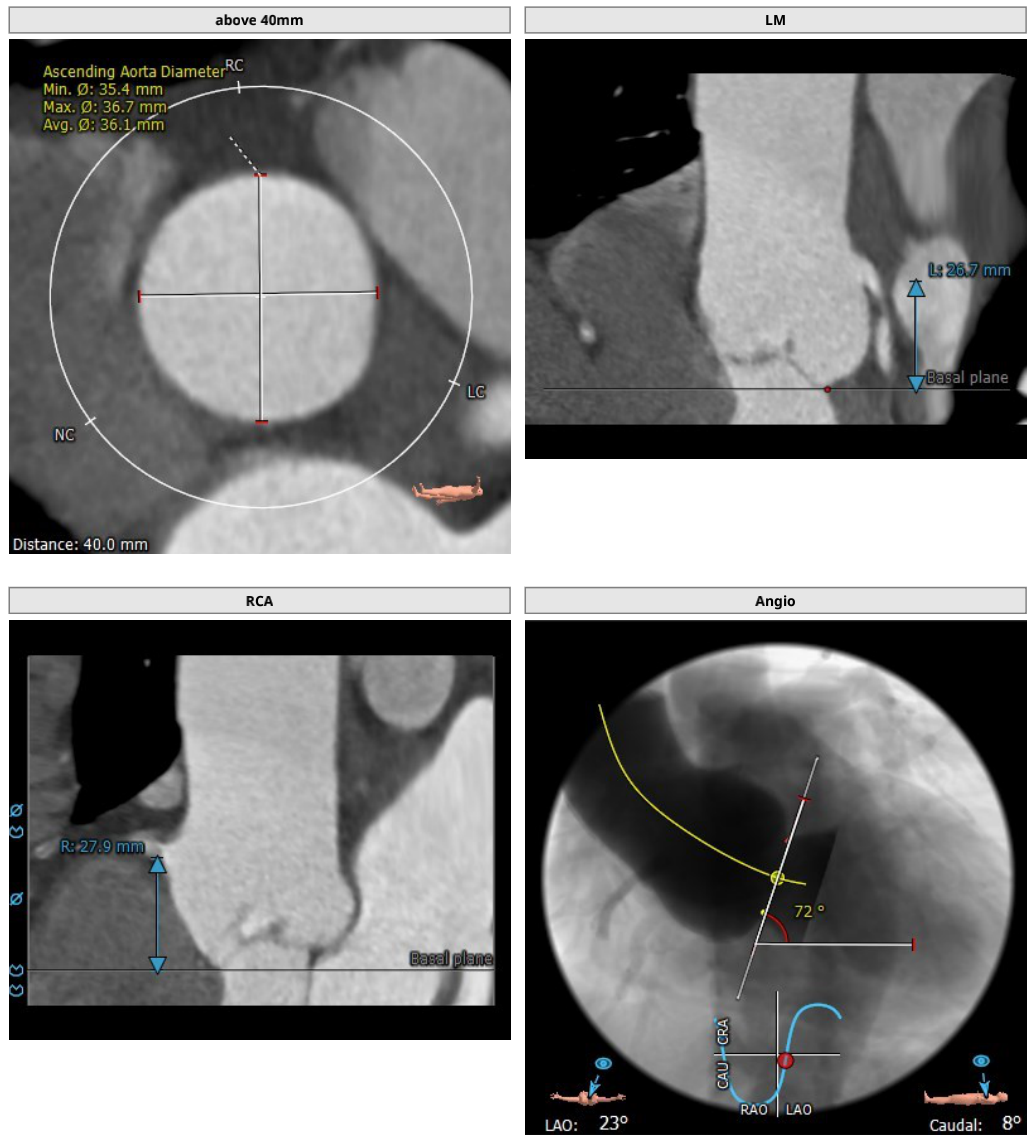

主动脉根部CT解剖影像

影像分析提示为三叶瓣结构,瓣叶无增厚及钙化,根据瓣环平面周长所得直径:24.3mm,左室流出道明显大于瓣环平面呈喇叭形,STJ无明显内收与升主动脉呈直筒形,左右冠开口高度可,窦部空间大,心脏角度72度横位心。

瓣叶无钙化/增厚,左室流出道、窦管交界及升主缺乏明确锚定区域,根部结构呈两头宽、中间窄的形态,瓣中瓣可能极大。窦部空间大、呼吸心跳运动下输送器定位困难,考虑瓣中瓣策略。